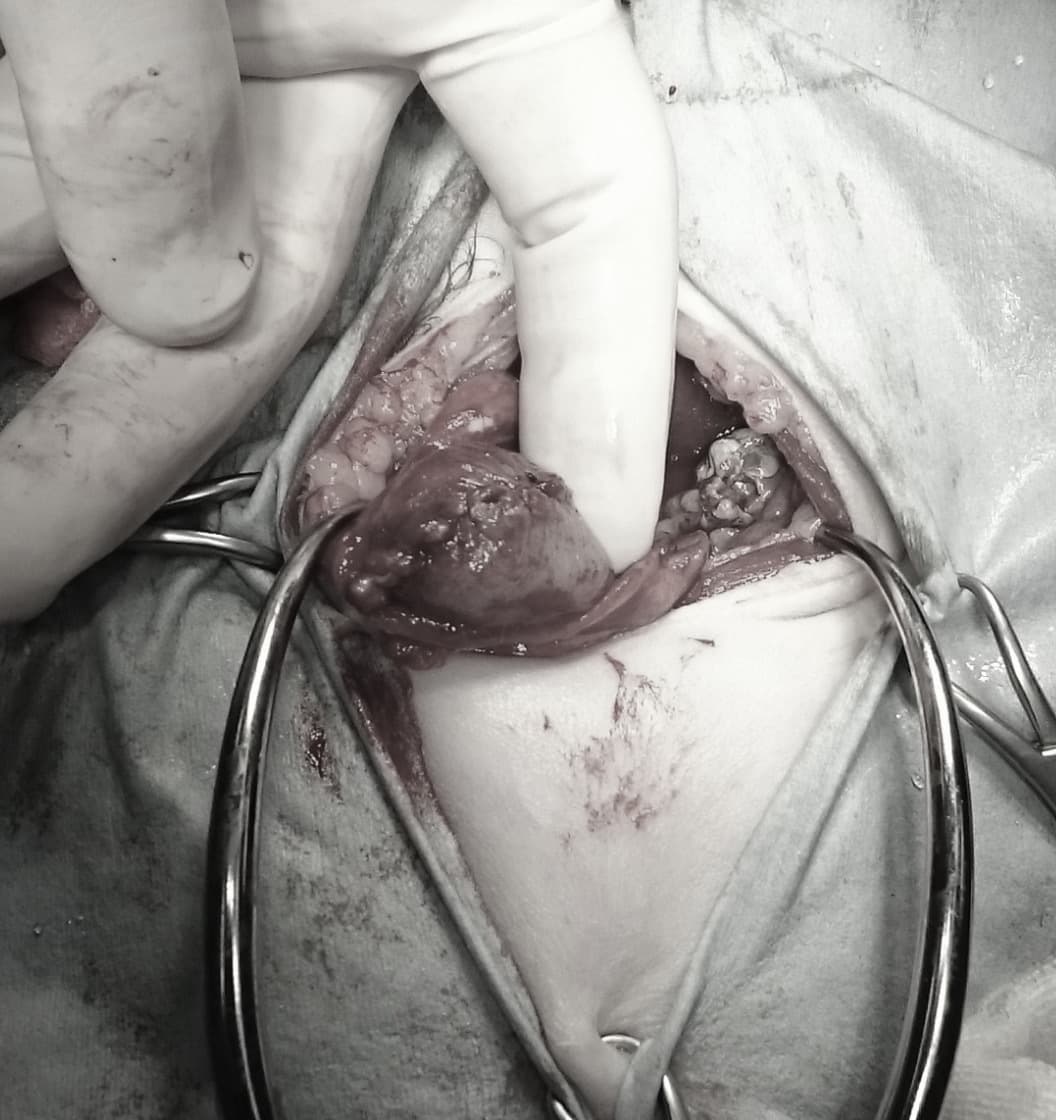

術前レントゲン

腹部臓器が胸腔内に脱出し、腹部と胸部の境界および心臓や肺の陰影が不明瞭になっています。また、胸腔内に消化管のガス陰影が認められます。

術中写真

横隔膜に開いた穴です。手術により脱出した腹部臓器を腹腔内に戻し、穴を縫合して塞ぎます。